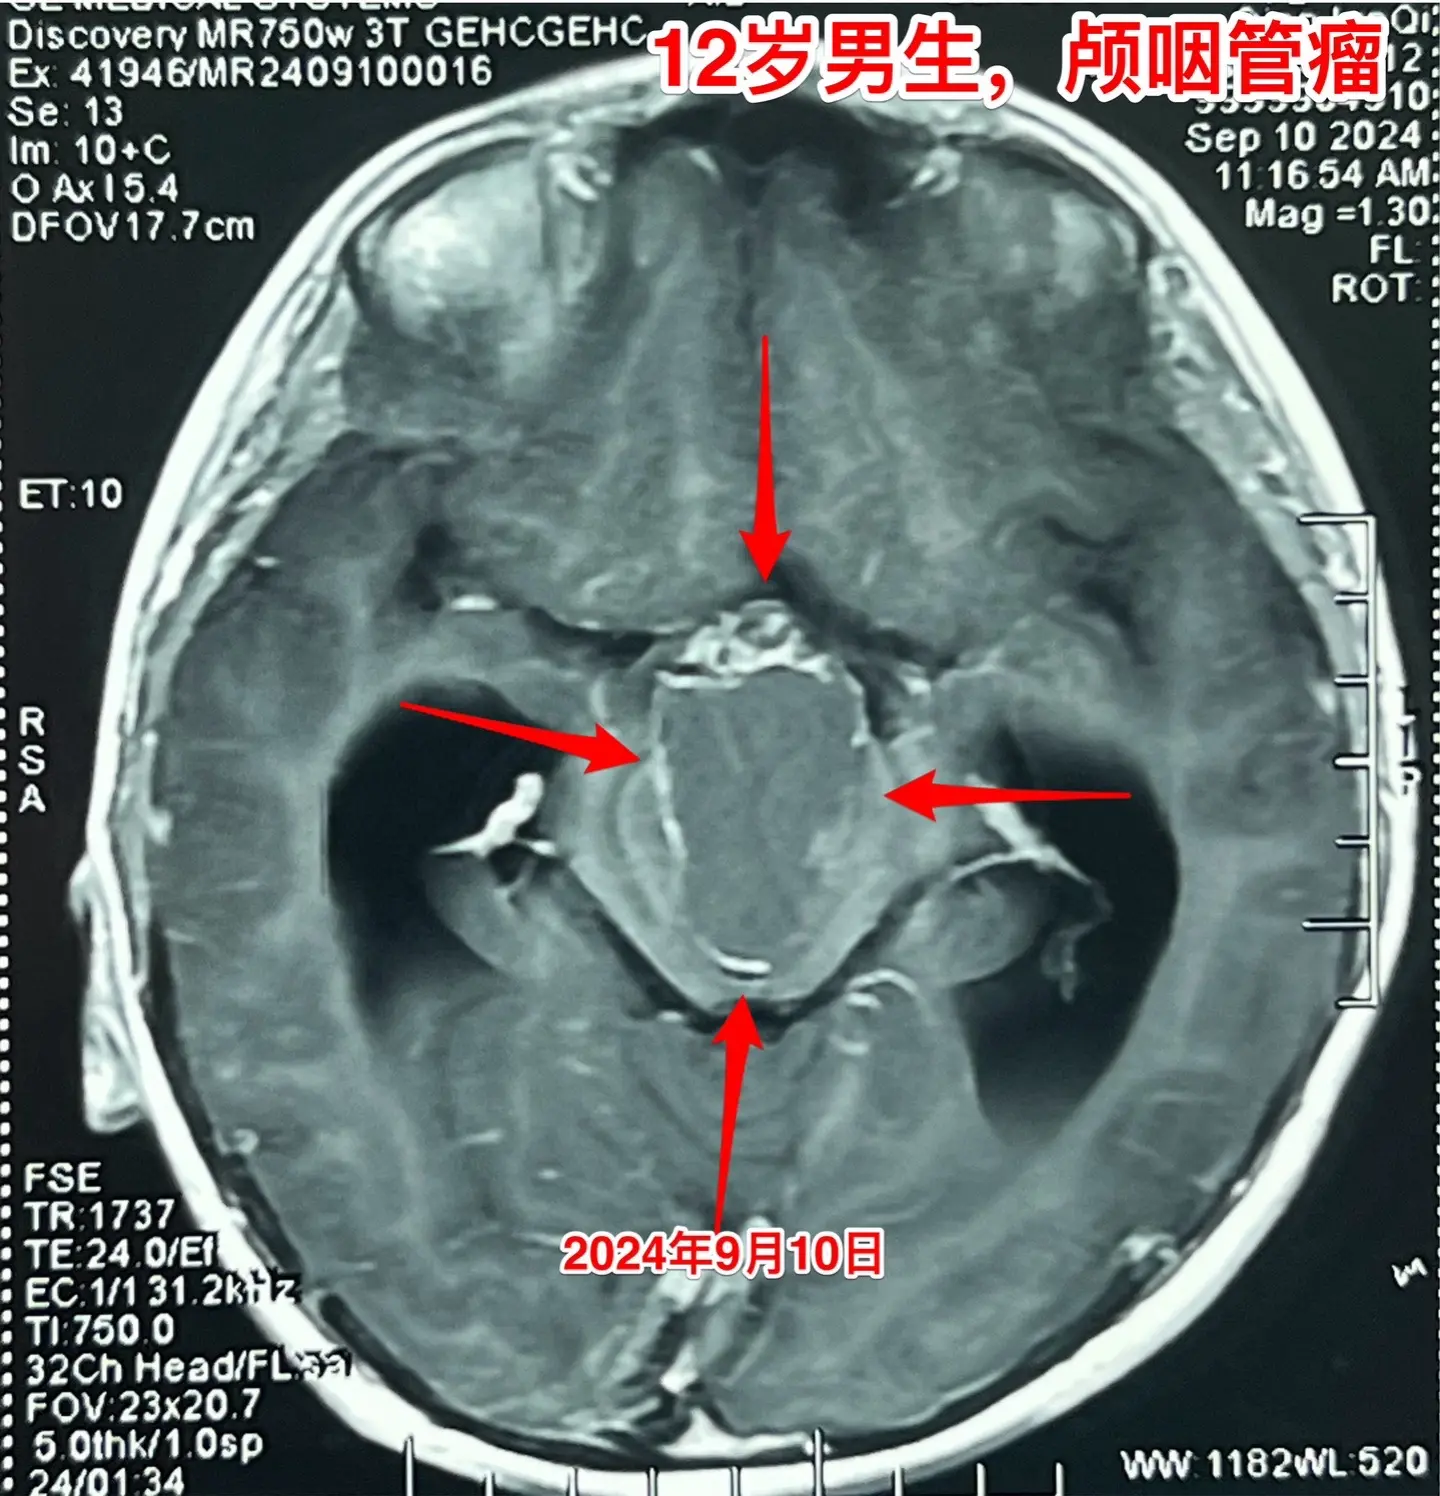

12岁南京男孩子头痛、呕吐。平时感觉身体很好,9月7日因头痛、呕吐到医院检查发现脑部长了颅咽管瘤,并且有脑积水。 9月9日到我院住院。住院时头痛、呕吐症状减轻了。复查磁共振显示颅咽管瘤的形态稍有变化,脑积水似乎有减轻。测视力发现他的视力有下降。这个颅咽管瘤生长的时间预计有两年时间,患儿症状不严重,最终因脑积水出现头痛、呕吐症状才发病。仔细检查还是可以发现一些蛛丝马迹,比如视力下降。颅咽管瘤有时会自动变小,很可能是肿瘤囊破裂了。囊变小了,脑积水就减轻了,头痛、呕吐症状就减轻了。 9月19日行开颅手术,将颅咽管瘤完全切除。手术后患者感觉视力有好转。希望肿瘤永不复发。